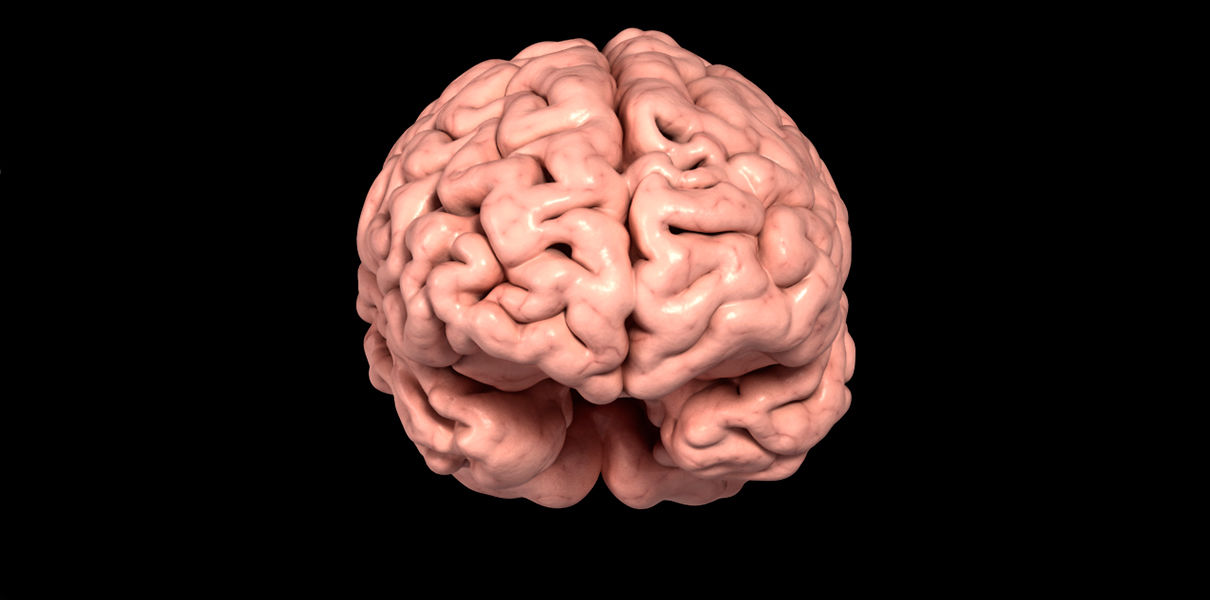

Легкие рисунки головного мозга: Пошаговые инструкции